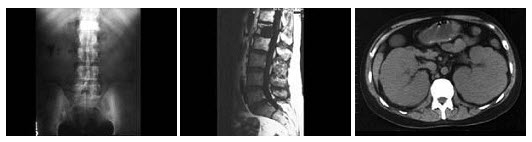

D.恶性淋巴瘤

男,38岁,进行性肾衰竭,有淋巴瘤病史,行腹平片、CT及MRI检查如图所示,下列说法正确的是()

A.CT示双肾对称性增大

B.MRIT1WI示L1椎体可见局灶性低信号改变

C.考虑为肾淋巴瘤,且淋巴瘤累及L1椎体